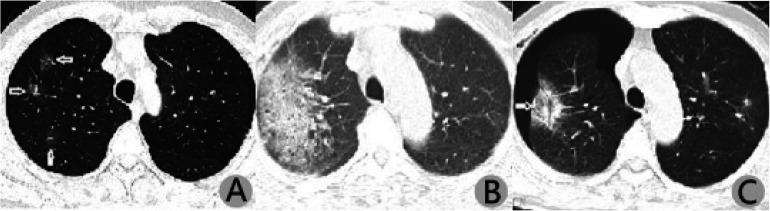

Microwave ablation has become an alternative treatment for pulmonary ground-glass nodules (GGN) and is widely accepted by clinicians. However, its effect on lung function remains unknown. Therefore, this retrospective study aimed to explore pulmonary function changes and associated risk factors in patients undergoing computed tomography (CT)-guided microwave ablation (MWA) for treating pulmonary GGN. Thirty-five patients diagnosed with pulmonary GGN on thin-layer chest CT and enhanced CT were examined. Patients unable or unwilling to undergo thoracoscopic surgery underwent CT-guided simultaneous percutaneous core needle biopsy and MWA. Pulmonary function tests (PFT) were performed before ablation and 3 days and 6 months post-ablation. Forced expiratory volume in one second (FEV1), FEV1%, forced vital capacity (FVC), maximal voluntary ventilation (MVV), and peak expiratory flow (PEF) values pre- and post-MWA were analysed. Linear regression analysis was used to examine the correlation between ablation volume and changes in PFT findings 3 days post-ablation. Associations between patient characteristics, rates of postoperative complications, and PFT findings were analysed. Forty-eight lesions were completely ablated and examined intraoperatively. There were significant differences in pre- and post-operative PFT findings on day 3 but not at 6 months. The mean ablation volume after 3 days of 11.4 ± 6.3 cm was positively correlated with changes in FEV1, MVV, and PEF values. Patients' age (mean, 59.4 ± 13.0 years) positively correlated with changes in PEF values. The rates of change in FVC and MVV values were significantly higher with multiple pulmonary nodules than with isolated pulmonary nodule. PFT findings were similar between patients who experienced or did not experience complications (eg, pneumothorax and pleural effusion). Pulmonary function could be impaired shortly after MWA. PFT findings may correlate with age, ablation volume, and number of ablated lesions. In most patients, pulmonary function returned to the preoperative state after 6 months.

微波消融已成为治疗肺部磨玻璃结节(GGN)的一种替代治疗方法,被临床医生广泛接受。然而,其对肺功能的影响尚不清楚。因此,本回顾性研究旨在探讨 CT 引导下微波消融(MWA)治疗肺部 GGN 患者的肺功能变化及其相关危险因素。

对经薄层胸部 CT 和增强 CT 诊断为肺部 GGN 的 35 例患者进行了检查。对于不能或不愿接受胸腔镜手术的患者,进行 CT 引导下经皮同轴芯针活检和 MWA。在消融前和消融后 3 天和 6 个月进行肺功能检查(PFT)。分析 MWA 前后的 1 秒用力呼气量(FEV1)、FEV1%、用力肺活量(FVC)、最大自主通气量(MVV)和呼气峰流量(PEF)值。采用线性回归分析评估消融体积与 3 天 PFT 检查结果变化之间的相关性。分析患者特征、术后并发症发生率与 PFT 检查结果之间的关系。

48 个病灶完全消融并在术中检查。术后 3 天的 PFT 检查结果与术前有显著差异,但在 6 个月时无差异。术后 3 天的平均消融体积为 11.4±6.3cm,与 FEV1、MVV 和 PEF 值的变化呈正相关。患者年龄(平均 59.4±13.0 岁)与 PEF 值的变化呈正相关。多发肺部结节患者的 FVC 和 MVV 值变化率明显高于孤立性肺部结节患者。有或没有并发症(如气胸和胸腔积液)的患者的 PFT 检查结果相似。

MWA 后肺功能可能会短暂受损。PFT 检查结果可能与年龄、消融体积和消融病灶数量有关。在大多数患者中,肺功能在 6 个月后恢复到术前状态。